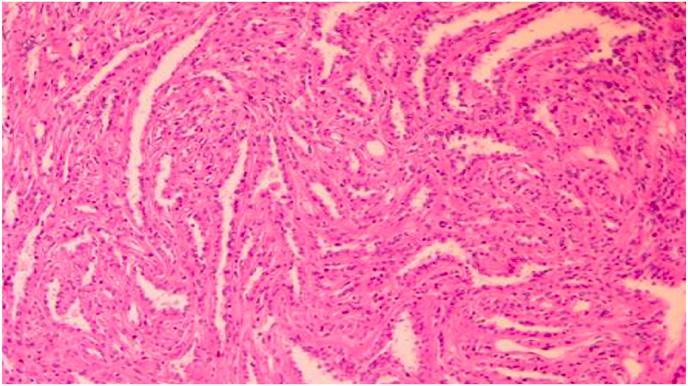

Rectorrhagia revealing synchronous colonic adenocarcinoma and papillary renal cell carcinoma type 1, an exceptional case report.

Colorectal cancer (CRC) is the most prevalent type of cancer affecting the gastrointestinal tract. The synchronous occurrence of CRC and renal cell carcinoma is rare, and even rarer when the renal cell carcinoma is of papillary origin, with only two cases reported in the literature. The synchronous detection of colon cancer and other primary tumors has been extensively studied and reported in the literature, either falling within the framework of well-defined clinical syndromes such as Lynch syndrome or occurring sporadically. This article aims to report and expose a literature review of the synchrony of colorectal cancer and renal carcinoma.